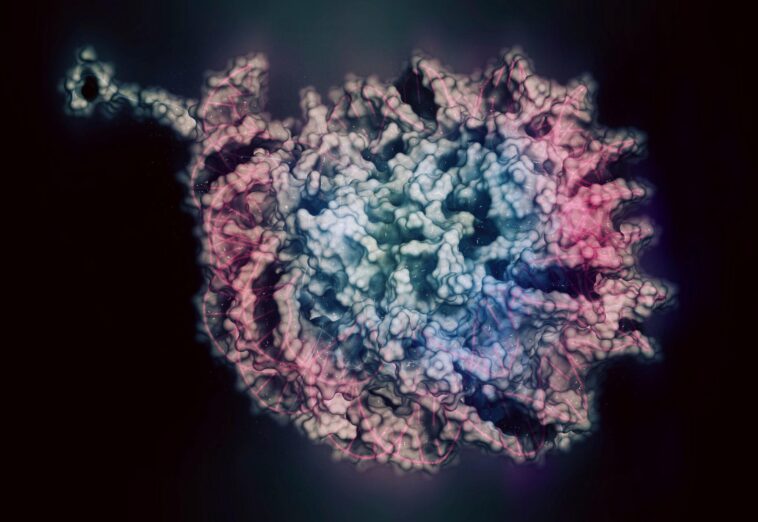

L’épigénétique implique des processus chimiques qui régulent l’activité des gènes, permettant à nos cellules, tissus et organes de s’adapter aux changements environnementaux. Cependant, ce bénéfice adaptatif présente un inconvénient : la régulation épigénétique est plus susceptible d’être perturbée par les toxines que la séquence génétique relativement stable de ADN.

Impact épigénétique du formaldéhyde

En guise de synthèse de la recherche, le Dr Esteller souligne que « nous avons découvert que le formaldéhyde est un inhibiteur de la protéine MAT1A, qui est le principal producteur de S-Adénosyl-L-Méthionine (SAM) et que cette dernière molécule est la protéine universelle. donneur du groupe chimique « méthyle » qui régule l’activité épigénétique. Plus précisément, nous avons constaté que l’exposition au formaldéhyde induisait une réduction de la teneur en SAM et provoquait la perte de méthylation des histones, des protéines qui emballent notre ADN et contrôlent la fonction de milliers de gènes.

Au total, ces travaux révèlent un aspect encore plus préoccupant de la toxicité du formaldéhyde. Le Dr Pontel le résume ainsi : « Nous avons découvert que le formaldéhyde a la capacité de modifier le paysage épigénétique de nos cellules, ce qui pourrait contribuer aux propriétés cancérigènes bien documentées du formaldéhyde. »